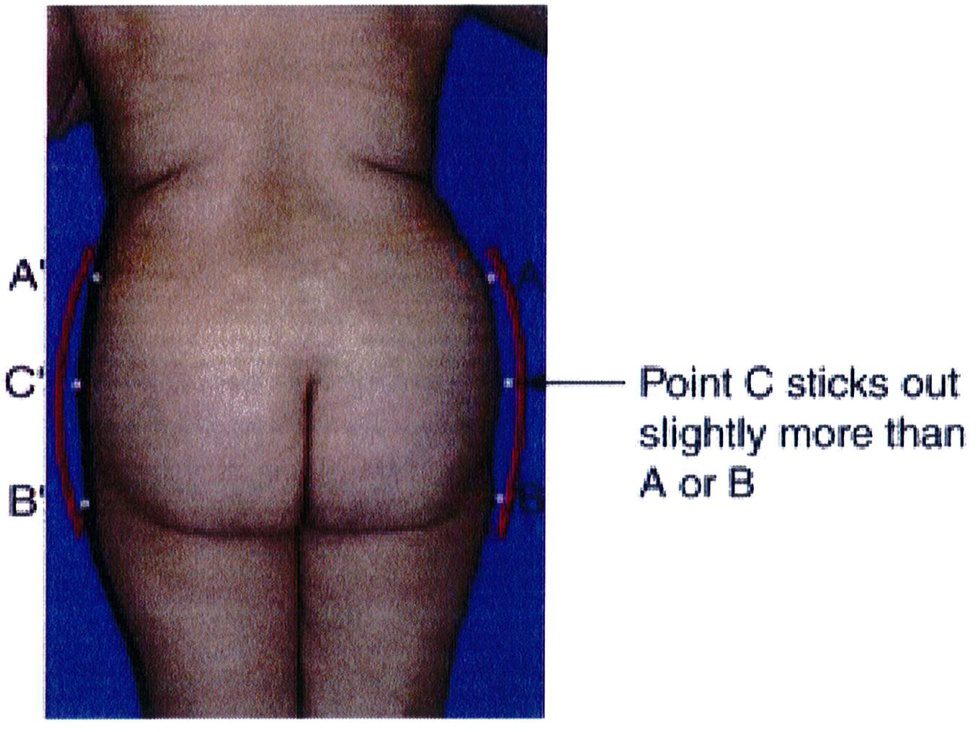

Xác định điểm trên cùng và dưới cùng của khối cơ Cũng như điểm sát cùng bên trong và bên ngoài. Từ đó xác định mối tương quan giữa chiều cao và chiều rộng (tỉ số cao/rộng). Thông thường chúng sẽ được chia thành 3 nhóm là ngắn/ thấp (tỉ số 1:1), cao (tỉ số 2:1) và trung gian (nằm giữa 2 tỉ số trên) (Xem hình 7 và 8). Một cơ mông lớn ‘lý tưởng’ sẽ thuộc nhóm trung gian, nhưng thường nghiêng về nhóm cao (2:1) (Xem hình 1A).

sẽ kêt luận đây là cơ mông có chiêu rộng hẹp. Nếu nó đi qua đường giữa mông này khoảng 10-30% thì được quy về chiều rộng bình thường. Và nếu vượt trên khoảng 40-50% thì được gọi là rộng. Mông đạt tiêu chuẩn thẩm mỹ ở người trẻ thuộc nhóm chiều rộng bình thường, và nếp lăn mông bên dưới chạy đến đường giữa hoặc chỉ vượt qua đường giữa mông đó 1 đoạn ngắn (Hình 1A).

Để xác định chiều rộng của khối cơ, vẽ 1 đường thẳng ở giữa mông (song song với đường liên mông). Sau đó xác định chiều rộng của nền khối cơ mông lớn từ đường giữa của cơ thể. Nếu đường đo nền khối cơ này (như hình 13, ảnh thứ 2 từ trái sang) không vượt quá đường thẳng vừa vẽ, chúng ta

Narrow base (50% line) Normal base Wide base (10-30% beyond central line) (40-50% beyond central line)

Hình. 17. Cách xác định chiều rộng phần nền khối cơ mông: hẹp, trung bình/ bình thường, hoặc rộng.

Narrow base(50% line : Hẹp (50% đường giữa) Normal base(10-30% beyond central line): Trung bình (vượt đường giữa 10- 30%) Wide base (40-50% bevond central line): Rôna (vươt đường aiữg 40-50% )